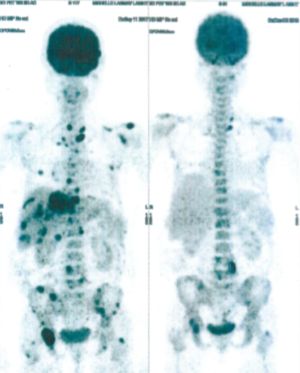

CASE NO: 2 (HEPATOCELLULAR CARCINOMA)

A 40+ man with hepatocellular carcinoma, an incurable cancer. After 2 treatment, the activity of the hepatocellular carcinoma is less.

CASE NO: 2 (HEPATOCELLULAR CARCINOMA) - After a few more treatments

After another few treatment, the activity of the hepatocellular carcinoma is much less. The patient never came back for further treatment, but this case, and case no: 1, shows that incurable hepatocellular carcinoma, often seen in hepatitis B and C patients, can be cured.

CASE NO: 3 (PROSTATE CANCER)

A middle-aged man with castration resistant prostate cancer, having failed all currently available cancer treatment, was very weak, and getting worse every day. The PET/CT scan showed he had massive bone metastases. After a few treatment, all the bone metastases went into remission. About 6 months later, he is still in remission.